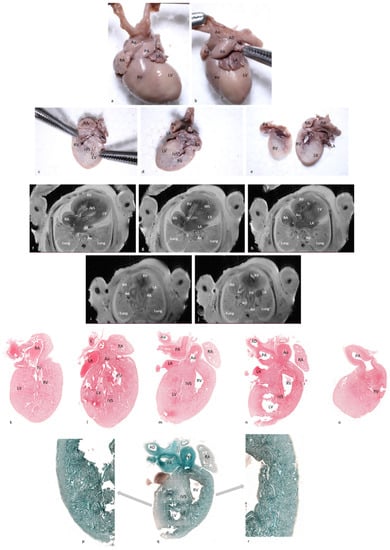

In case No.11, both methods diagnosed the complete atrioventricular canal but pm-MRI also diagnosed a hypoplastic left ventricle as well as an overriding aorta and arterial duct agenesis. Comparative images with observed lesions are depicted in Figure 5. Additionally, in case No.12, though both methods described most of the lesions, 4CCD failed to describe bilateral ventricular hypertrophy and a ventricular septal defect. Thus, 4CCD overdiagnosed an aortic valve stenosis and tricuspid valve stenosis. Comparative images are presented in Figure 6. Therefore, as shown in Table 2, the lowest sensitivity rate was observed in examining the arterial duct and left atrium. The disagreement was in two out of three cases, presenting anomalies on pm-MRI (cases No. 7 and 11). For the conventional dissection method, a minimum of six fine sections are required for evaluation of the atria, ventricles, and outflow tracts, whereas for the 4CCD method, only two parallel sections are required. External cardiac examination was described as a common step for both methods. Microscopic examination required more time for the 4CCD method, especially for malformed hearts, but it did not surpass the entire time needed for the stereomicroscopic cardiac examination. Our subjective assessment revealed that the 4CCD method required less time for examining fetal hearts than the conventional inflow–outflow method for very small fetal hearts.

Figure 6.

Comparative examination of pm-MRI at 7T (T2, WI) and four-chamber cardiac dissection of a 16-week gestation-age male with 18 Trisomy resulted from a therapeutic interruption of pregnancy (case 12 in the text). (a,b) Macroscopic anterior and antero-lateral view of the fetal heart. Thickening of great vessels and biventricular fibroelastosis. Thickened endocardium visible on pm-MRI images (f,g,h,i,j) but also on microscopic images ((p)—Masson’s trichrome stain, 1.4×; (q)—Masson’s trichrome stain, 0.7×; and (r)—Masson’s trichrome stain, 2.7×). Additionally, the thickening of great vessels, which can be observed on pm-MRI images, microscopy slides ((k)—hematoxylin-eosin stain, 0.6×; (l)—hematoxylin-eosin stain, 0.6×; (m)—hematoxylin-eosin stain, 0.5×; (n)—hematoxylin-eosin stain, 0.7×; and (o)—hematoxylin-eosin stain, 0.8×), and also on macroscopic sections (c,d,e). Abbreviations: RA—right atrium, RV—right ventricle, LA—left atrium, LV—left ventricle, Ao—aorta, PA—pulmonary artery, AD—arterial duct, IAS—interatrial septum, IVS—interventricular septum, IVC—inferior vena cava, SVC—superior vena cava, RPA—right pulmonary artery, RPV—right pulmonary veins, LPA—left pulmonary artery, TV—tricuspid valve, MV—mitral valve, I—infundibulum, E—esophagus, and B—bronchi.